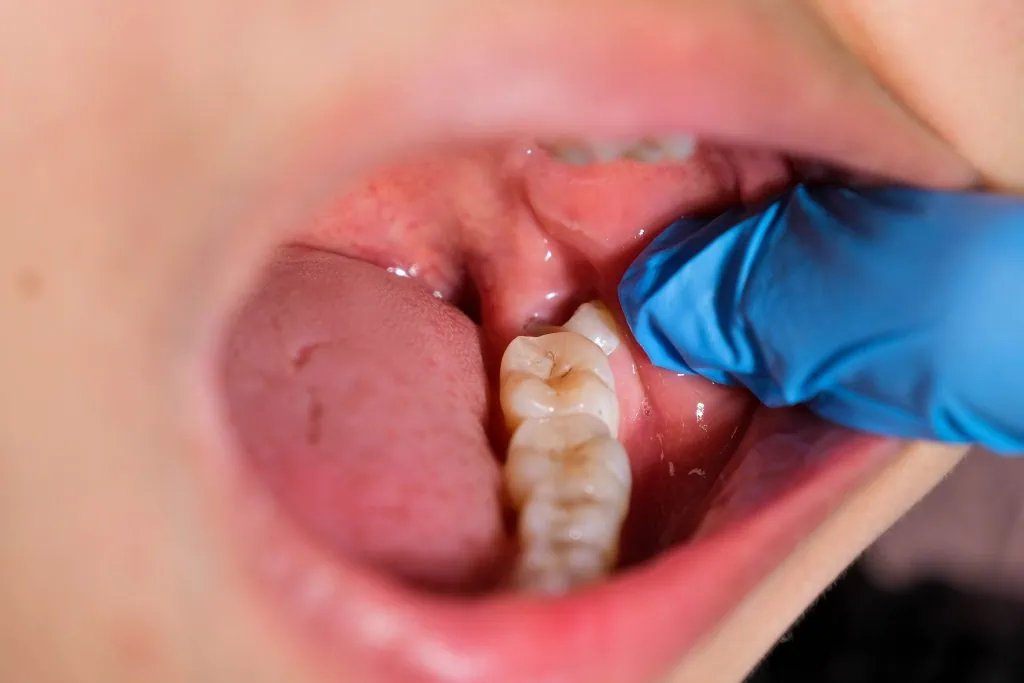

Khi răng khôn mọc lệch, mảng bám và vi khuẩn dễ tích tụ ở vùng nướu trùm phía trên, gây viêm nhiễm tái phát. Người bệnh thường gặp sưng, đau răng khôn, hôi miệng và khó há miệng. Nếu không xử lý, tình trạng này có thể lan rộng, gây viêm mô tế bào hoặc áp xe quanh thân răng.

Một biến chứng khác là sâu răng lây lan sang răng số 7 do răng khôn mọc nghiêng, khiến việc vệ sinh trở nên khó khăn. Khi sâu lan đến tủy, cả hai răng đều có nguy cơ phải nhổ bỏ, ảnh hưởng trực tiếp đến chức năng ăn nhai.